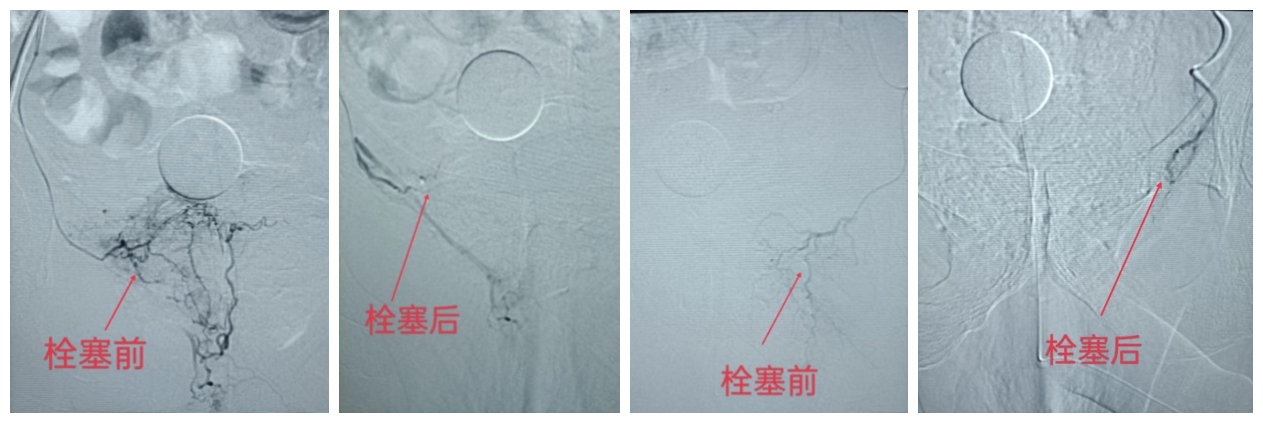

8月8日我院介入血管科完成本院第一例前列腺增生动脉微创介入栓塞手术治疗,手术过程顺利,术后无不良反应,效果明显。此次手术也是该患者1个月内在我科进行的第4次介入微创手术治疗。患者:相某 男 58岁,前列腺增生8年,近1年来尿频、尿急、夜尿增多、排尿困难等症状明显加重。间断药物治疗效果不佳。7月9日因“血尿伴高热3天”我院就诊,当天检查血小板及肾功多项指标报危急值,其中血小板最低5×109。血红蛋白69g/l,收住肾内科后积极透析治疗,但患者一直血尿,血压低,心率快,一度处于失血性休克状态,共计输注红细胞悬液10u,血小板1个单位,止血药、升压药持续滴注。治疗期间双下肢出现重度肿胀,超声检查为:“双下肢严重血栓形成”。出血与血栓治疗方案完全矛盾,真是“屋漏偏逢连夜雨,船迟又遇打头风”,因患者病情危重,随时有生命危险,多科会诊均因麻醉风险高,不建议手术治疗。多次告病危,患者近乎绝望,家属已经要放弃治疗。随后请我科薛学文主任会诊,建议先行下腔静脉滤器置入防止肺动脉栓塞,再行膀胱动脉造影栓塞出血动脉。待出血平稳后再行血栓治疗。患者及家属反复商量后同意手术。7月12日手术穿刺颈内静脉先行下腔静脉滤器置入(因双下肢深静脉血栓形成),随后穿刺股动脉行膀胱动脉造影,栓塞出血动脉。手术过程非常顺利,术后出血停止。经透析肾功能恢复,7月18日好转出院。出院后双下肢肿胀逐渐加重,1周后患者再次来院,要求血栓治疗,轮椅推入病房,双下肢高度肿胀已经无法行走,入院后急诊行下肢深静脉血栓抽吸,球囊扩张,置管溶栓,第二天肿胀很快减轻,但拔除尿管后,再次出现排尿困难。请泌尿科会诊后建议行前列腺手术治疗,患者及家属拒绝手术,但得知可以用介入微创手术治疗前列腺增生后欣然同意,因为前几次的介入治疗让他们看到了介入手术的微创及高效(不开刀,仅在局麻下穿刺约2mm的针眼完成手术治疗)。随后于8月8日在局麻下给予双侧前列腺动脉栓塞治疗,手术过程顺利,术后7天复查超声:前列腺体积明显缩小,为原来的46.8%(由术前的125.28cm3,缩小到58.752cm3。),轮椅推入病房,步行走出医院。介入手术不仅从死亡线上救回了他的生命,也解决了患者多年的顽疾,患者及家属非常满意,对介入治疗赞不绝口。

超声检查前列腺体积由术前的5.8*4.8*4.5cm缩小到术后5.4*3.4*3.2cm